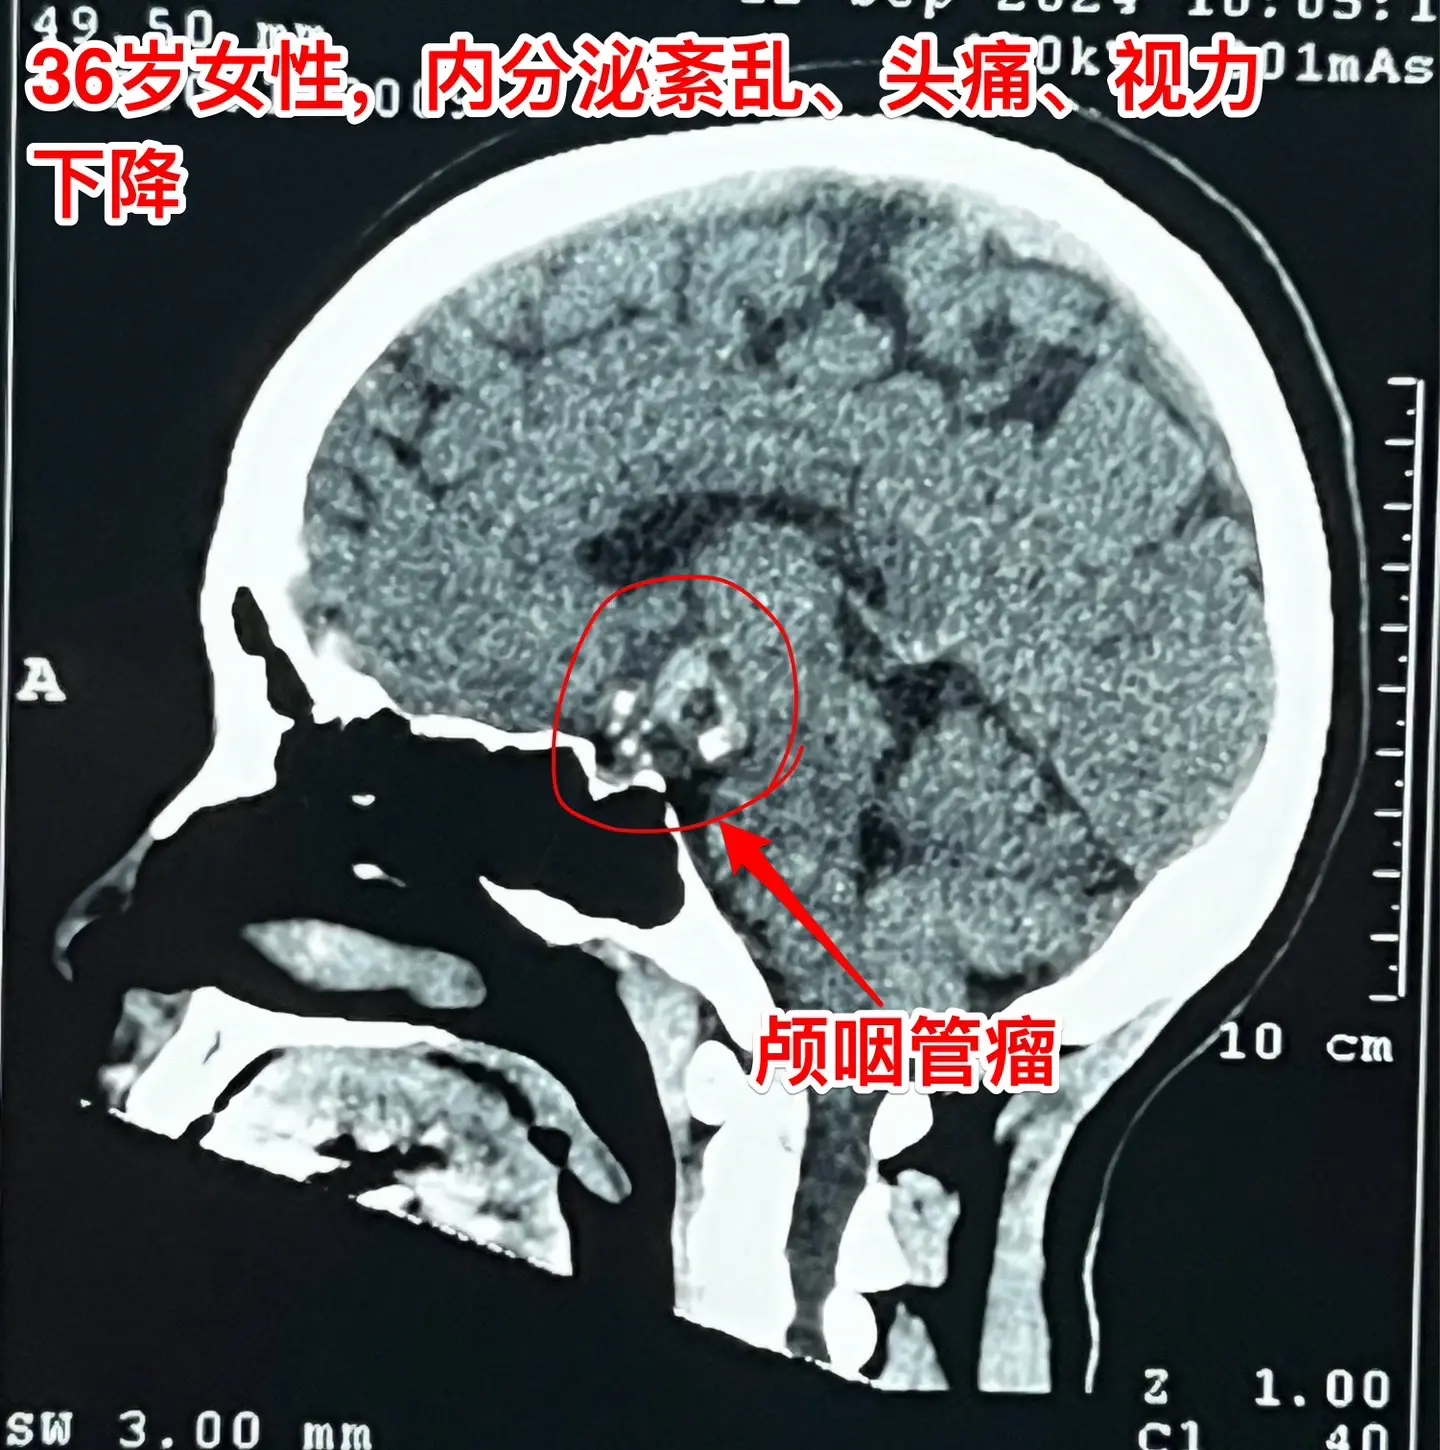

36岁玉溪市女性,颅咽管瘤手术后视力改善。一开始出现内分泌紊乱,随后出现头痛、视力下降。发现颅咽管瘤后于9月11日到我科住院,因为发烧,等到9月24日才作了手术。 好饭不怕晚!手术很顺利,肿瘤得到完全切除,垂体柄保留了30%。手术后病人的身体恢复很快,视力也好转了。